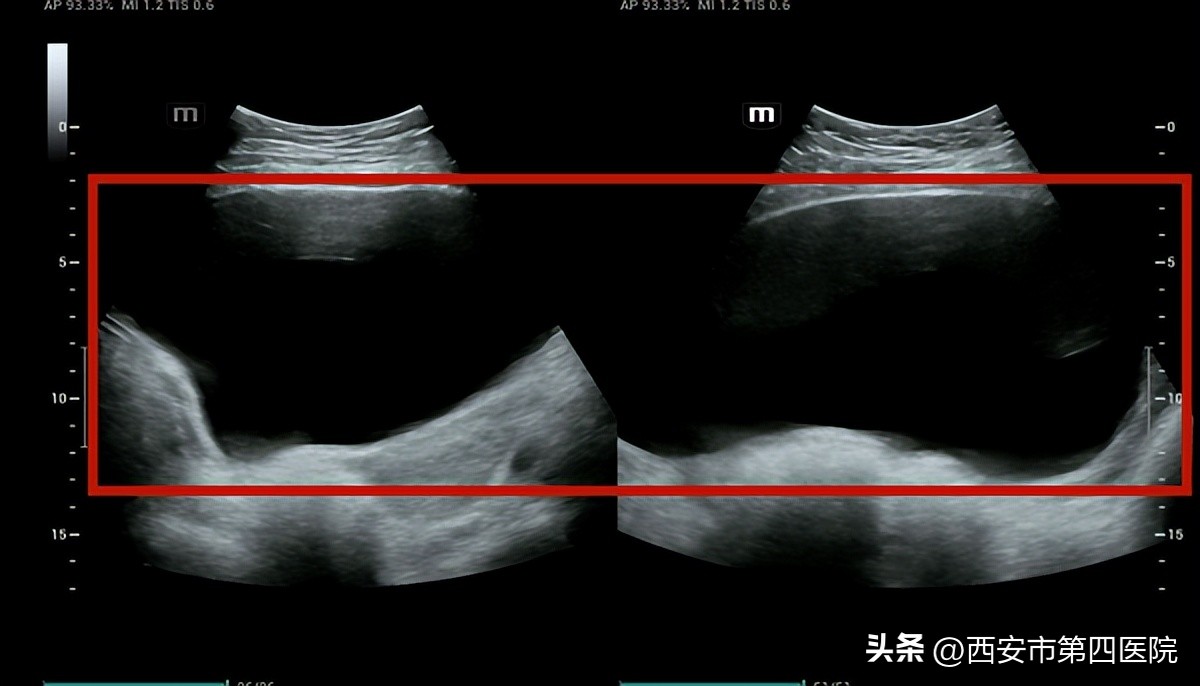

医生建议进行B超检查,提示“膀胱残余尿879ml”,根据情况这属于典型产后尿潴留。

成人膀胱容量平均为300到500ml,大约尿量在150到250ml会产生尿意,超过500ml会因膀胱张力过大而引发疼痛, 膀胱最大的极限是800ml。

女性的膀胱容量一般小于男性, 李女士膀胱残余尿已经到了极限,膀胱相当于被撑成一个大水球。 长时期如此,会使膀胱失去弹性,回缩都出现困难,尿道的括约肌也不再灵敏。

(上图红框部分为膀胱被尿液充盈暗区,下图红框为排尿后暗区消失)

3次治疗后排尿功能恢复正常,B超显示无残余尿 。李女士感慨:“终于不用插导尿管了!”